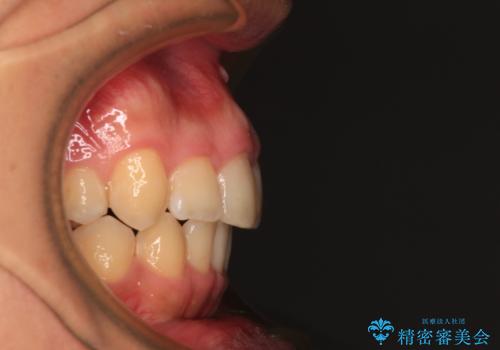

- 学生時代に抜歯矯正した歯列が後戻りしてきたとのことで来院された患者様です。

舌の突出癖が原因で上顎前歯が前方に移動したと考えられたため、舌のトレーニングを徹底して行っていただきながら、後戻りを解消していくこととしました。

マウスピース矯正でもワイヤー矯正でも対応可能でしたが、患者様の希望によりワイヤー装置による矯正治療を行うこととしました。

ワイヤー矯正ということで、上顎大臼歯を後方に移動するための補助装置を併用して、積極的に前歯を引っ込めていくこととしました。

上顎歯列全体がスムーズに後方移動でき、1年で治療を終えることができました。